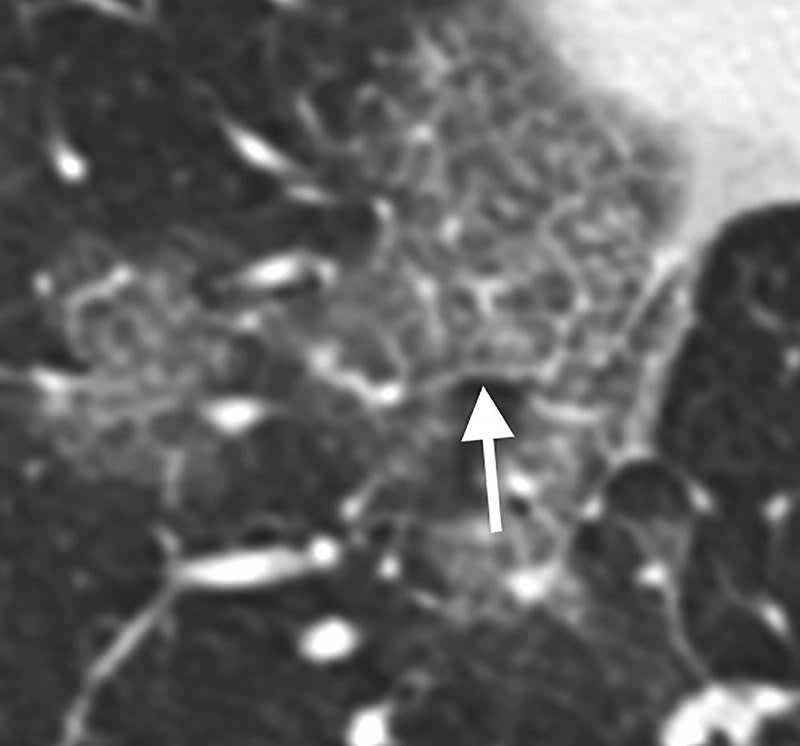

The analysis showed that 2019-nCoV typically manifests on CT with bilateral ground-glass and consolidative pulmonary opacities. Nodular opacities, crazy-paving pattern, and a peripheral distribution of disease may be additional features helpful in early diagnosis. The researchers also noted that lung cavitation, discrete pulmonary nodules, pleural effusions, and lymphadenopathy are characteristically absent in cases of 2019-nCoV. Follow-up imaging in seven of eight patients showed mild or moderate progression of disease as manifested by increasing extent and density of airspace opacities.